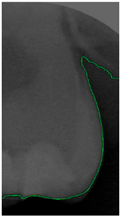

2.3.5. Canny Edge Detection

Since filtered and binarized images alone cannot enhance the features of dental calculus, this approach does not effectively improve the accuracy of machine learning. Therefore, this study employed edge detection to identify the contours of tooth edges, enhancing the regions of interest and thereby improving the accuracy of machine learning. The canny edge-detection algorithm applies non-maximum suppression to each pixel, retaining pixels with local maximum gradient values, which can produce continuous and accurate edges while demonstrating good resistance to noise. The edge-detection results are represented in green, as shown in Figure 8c. Finally, these results are overlaid back onto the original image, as illustrated in Figure 8d.

Figure 8.

Image-enhancement results: (a) binarization; (b) mathematical morphology; (c) added green line represents canny; (d) overlap onto the original image.